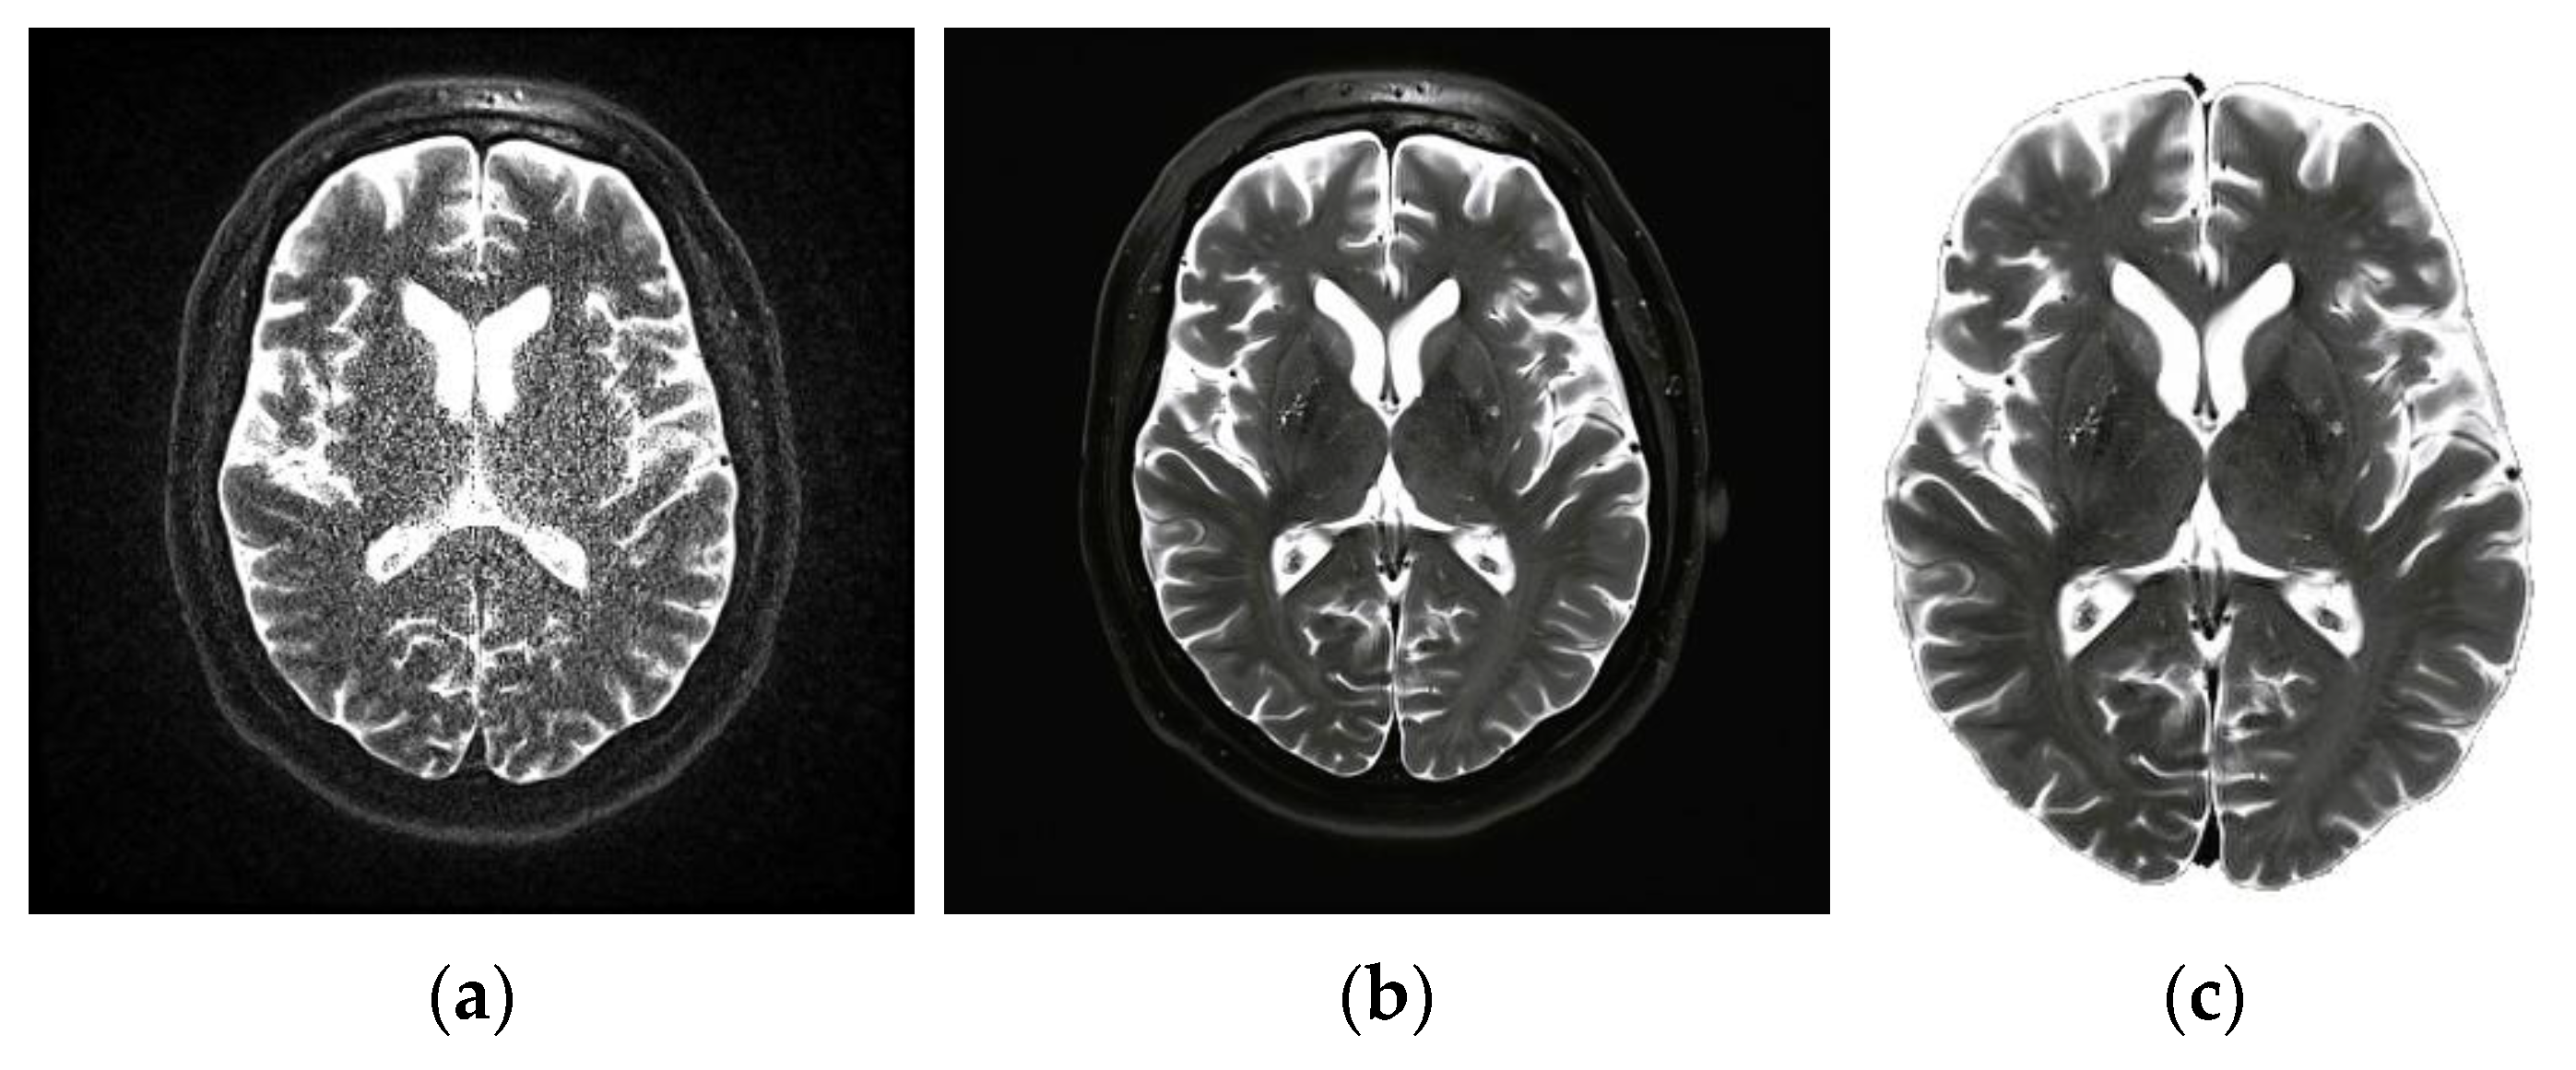

It is generally agreed that the first step is the most crucial of all the steps. This procedure was primarily geared toward enhancing the image quality by removing any noise or other unnecessary components already present in the image. Eliminating background noise is challenging, especially in therapeutic and diagnostic settings. The preprocessing step in magnetic resonance imaging (MRI) can be difficult due to some issues, including an inhomogeneous magnetic field, patient movement, and external noise. As a result, this work suggests using an adaptable filtering method. The median filter [31] retains the relevant information that is already there in the image while simultaneously reducing the amount of noise. When using this method, each pixel in the image is evaluated concerning the pixels surrounding it, and the results are categorized as noise. After that, the value of the median pixel relative to its neighbors is substituted for these pixels. The smoothing of images is a fundamental practical module that improves image quality by reducing the amount of noise in the picture. Figure 2a represents a noisy MRI image, and Figure 2b represents the filtered image. The filtering is an optional step, where based on the amount of noise, a filtering decision will be made. Following the filtering step, the presence of the skull should be eliminated from the brain’s MRI by using erosion and dilation procedures. The erosion technique erases both the foreground and background of the skull. The existence of a false background leads to the development of some aberrations in the tissues of the brain. A procedure known as dilation is used on the tissue that has been stretched out of its standard shape. Generally, this method is quite effective at removing the skull from the MRI. The result of this step is shown in Figure 2c.

Figure 2.

(a) Noisy MRI image, (b) filtered image, (c) and output of skull elimination.